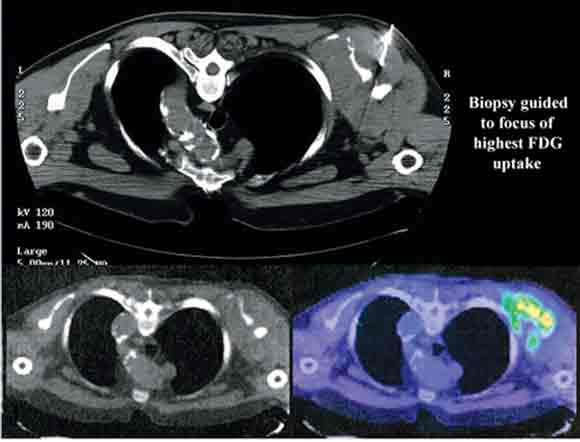

6 Positron emission tomography/computed tomography guided biopsy of a left scapular soft tissue mass

Such images allow representative histological sampling of the most metabolically active region within a heterogeneous mass lesion.

Attempts at histological characterisation can be problematic in patients with cancer. The availability of anatomical information from PET/CT can assist in selecting the most accessible mass for biopsy. After treatment, residual masses may not contain any active tumour, and the presence of residual uptake can guide which masses require biopsy. In addition, tissue heterogeneity is a common feature within individual malignant masses, particularly in sarcomas, where high-grade tumour can co-exist with acellular matrix components and low-grade tumour elements. Because of the high uptake of FDG in aggressive tumours, intermediate FDG uptake in low-grade tumours and very low FDG uptake in necrotic or fibrotic tissue, PET/CT imaging can be used to guide biopsy to the most metabolically active regions of structural masses (Box 6). This has two potential advantages: the likelihood of non-diagnostic biopsy may be reduced,16 and the biopsy will more likely reflect the most biologically active, and therefore prognostically significant, tumour elements.17,18